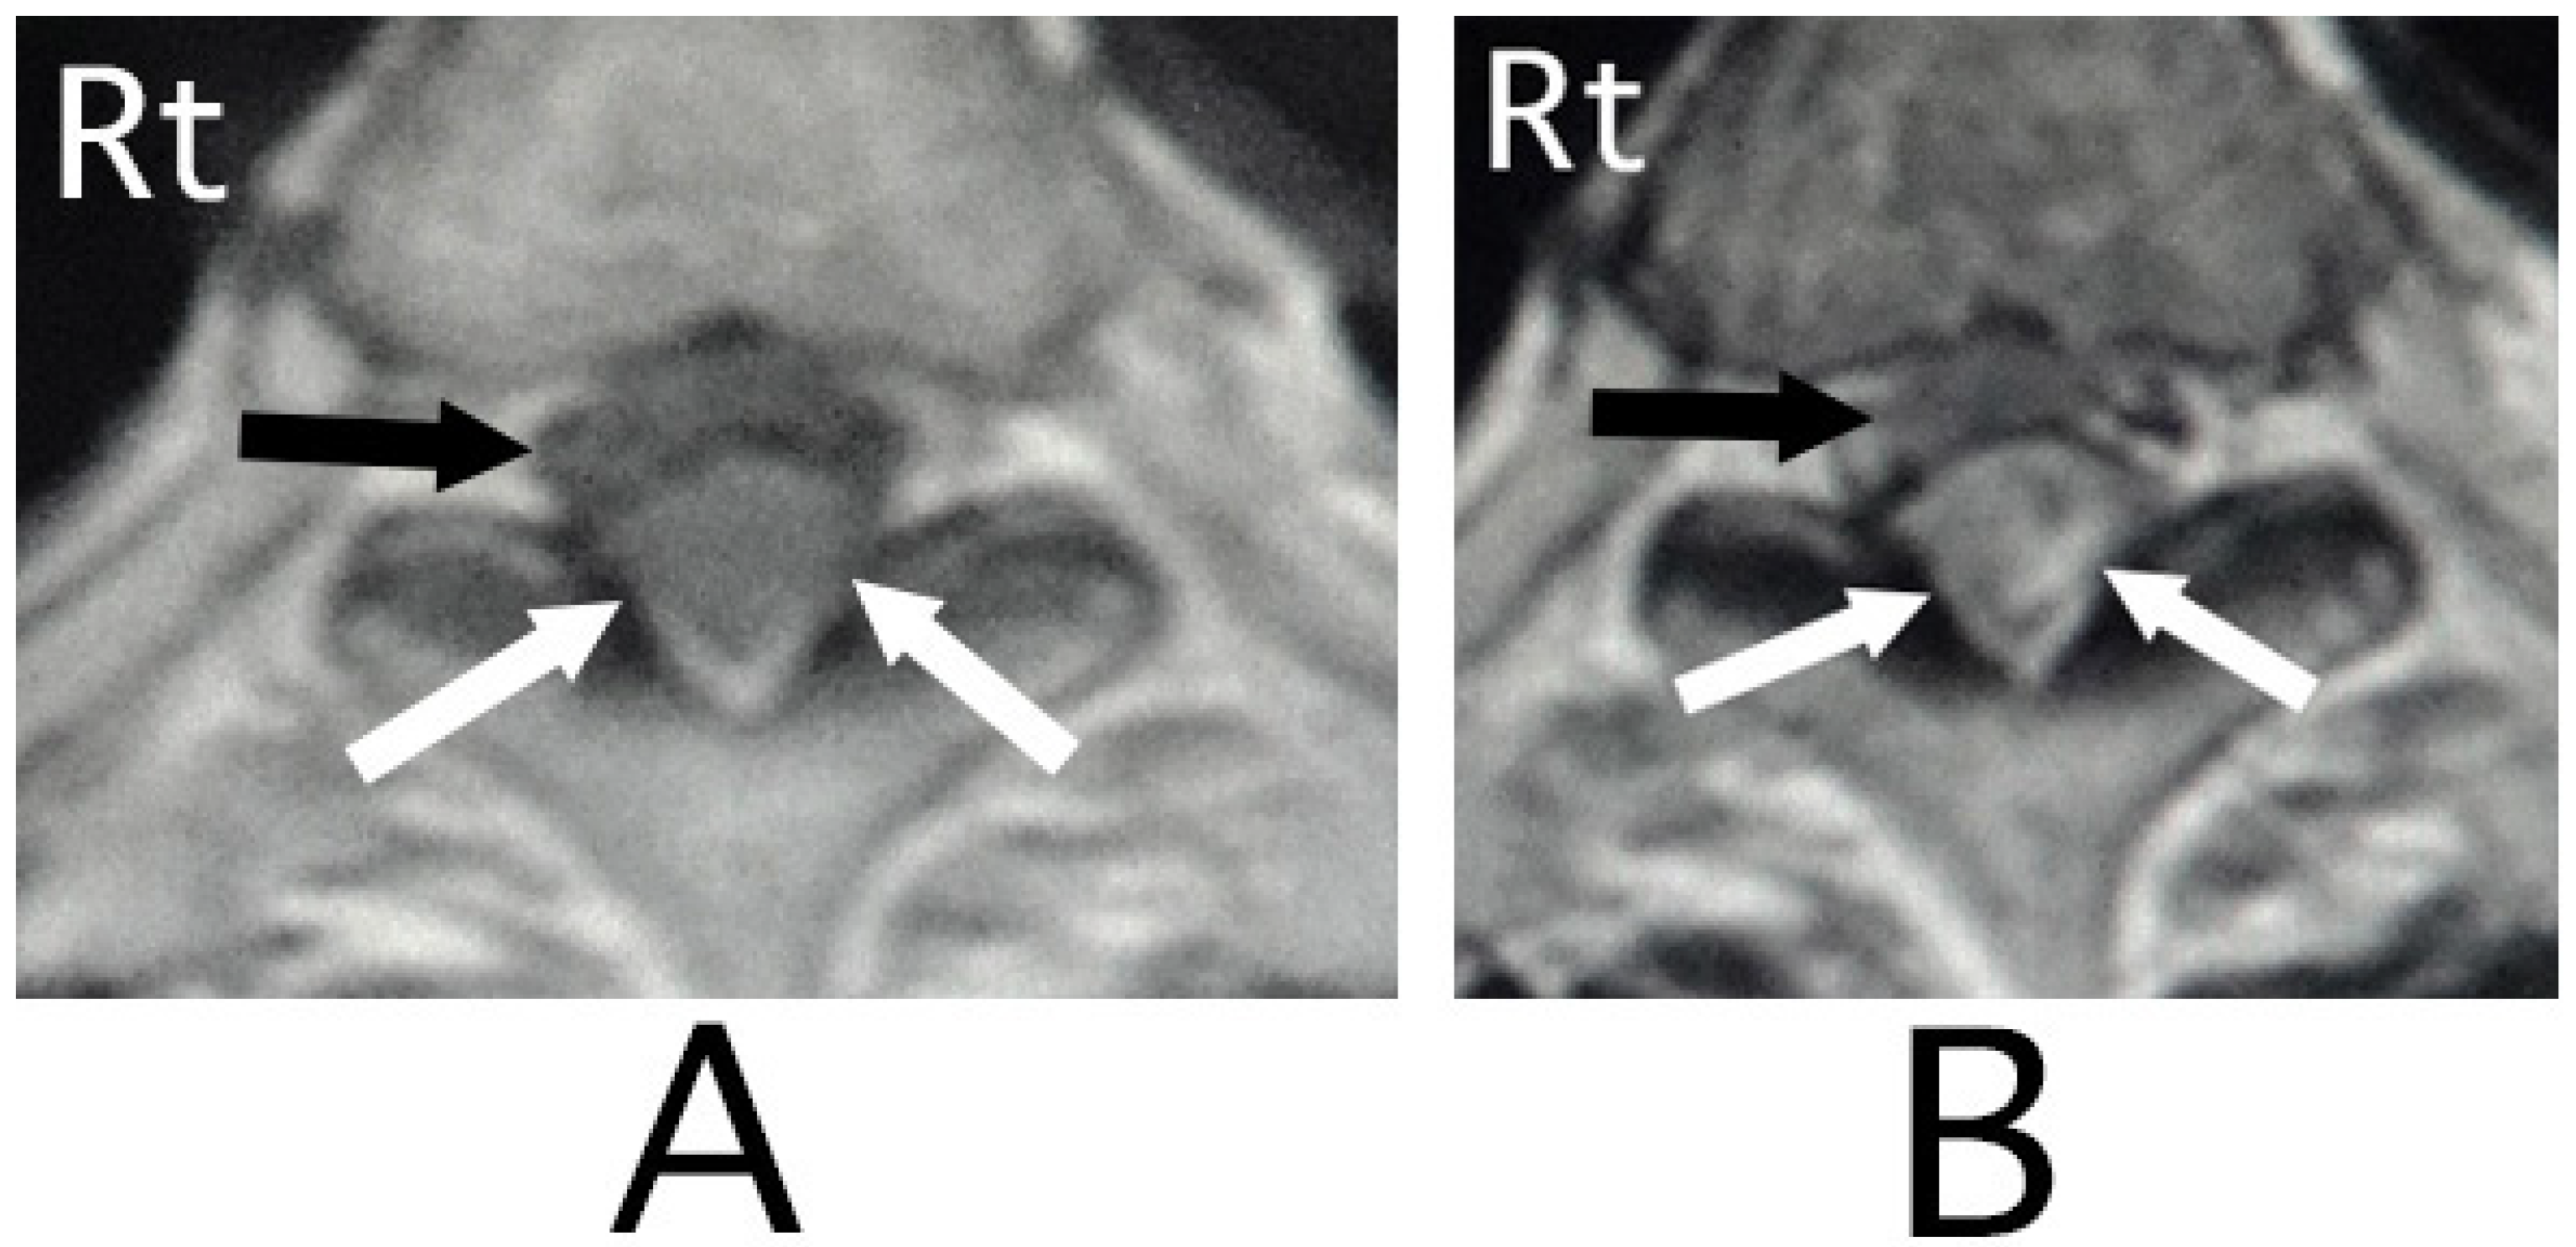

MRI of the spinal cord analysis was performed because the presence of acute lesions on the spinal cord was suspected, based on neurological findings and the clinical course. As a result, sagittal T1-weighted MRI showed an iso-intensity mass in the epidural space behind the spinal cord at the level from Th3 to Th6 (Figure 1A). Compression of the spinal cord was shown at the level between Th4 and Th6 (Figure 1A,B). The lesion was delineated as a high-intensity mass with heterogeneity and a superiorly adhered iso-intensity region in sagittal T1-weighted images (Figure 1B). Axial T1-weighted MRI showed an iso-intensity mass in the posterior part of the epidural space and a deviation of the spinal cord to the anterior direction (Figure 2A). The lesion was delineated as a heterogeneous high-intensity mass in axial T2-weighted MRI images (Figure 2B).

Figure 1. Sagittal MRI. An iso-intensity mass in the epidural space was shown behind the spinal cord at the level from Th3 to Th6 (white arrows) (T1-weighted image; (A)). The lesion was observed as a heterogeneous high-intensity mass (white arrows) and a superiorly adhered iso-intensity region (T2-weighted image; a black arrow) (B).